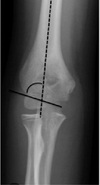

What is the normal carrying angle in men and women?

Men: 10-15 degrees Women: 15-20 degrees

How much varus/valgus is there at the distal humerus?

6 (6-8)degrees valgus. This differs from the actual carrying angle